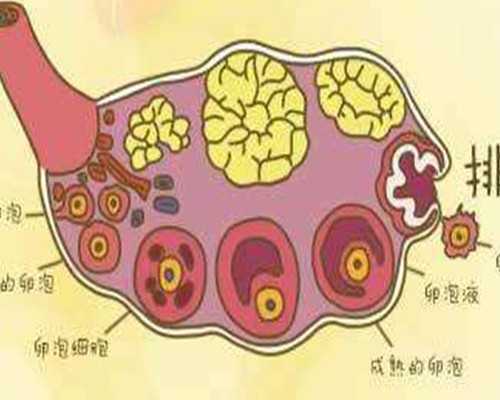

| 2 | 促排卵藥物和b超監測費用 | 不同的促排卵方案藥物種類不同,卵巢儲備功能和機體對藥物的敏感性也有所不同,而這使得每個患者的藥物種類和劑量也不同,因此費用也不同,所以,如果有試管指征,盡早在合適的年齡選擇試管嬰兒治療也是省錢的策略,約5000-13000元左右 |